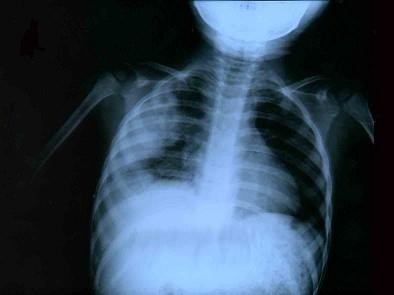

问题 2岁小儿突然高热、咳嗽,抗生素治疗12天仍未见效,且咳嗽气促加重。呼吸55次/min,心率160次/min,两肺可闻及细小水泡音。右上肺叩诊稍浊,呼吸音减弱,并可闻及湿啰音。胸部X线片示右肺散在小片状浸润,部分融合成片,右上肺大片浓密阴影,阴影内似有液气平,胸片见图。应考虑为 ( )

选项 A、革兰阴性杆菌肺炎 B、支原体肺炎 C、大叶性肺炎、脓胸 D、金黄色葡萄球菌肺炎、肺脓肿 E、病毒性肺炎、渗出性胸膜炎

答案 D